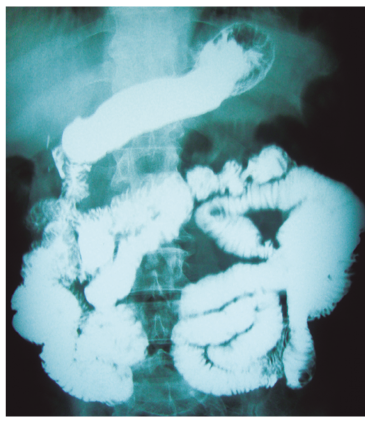

Se realiza TC (Figuras 1 y 2) que informa: en primera porción duodenal, a nivel de rodilla superior, divertículo de base ancha de 42 por 48 mm de diámetro, que luego de la administración de contraste se observa en toda su extensión.

El paciente presenta buena evolución postoperatoria, se realiza SEG control (Figura 4) postquirúrgico previo al alta.